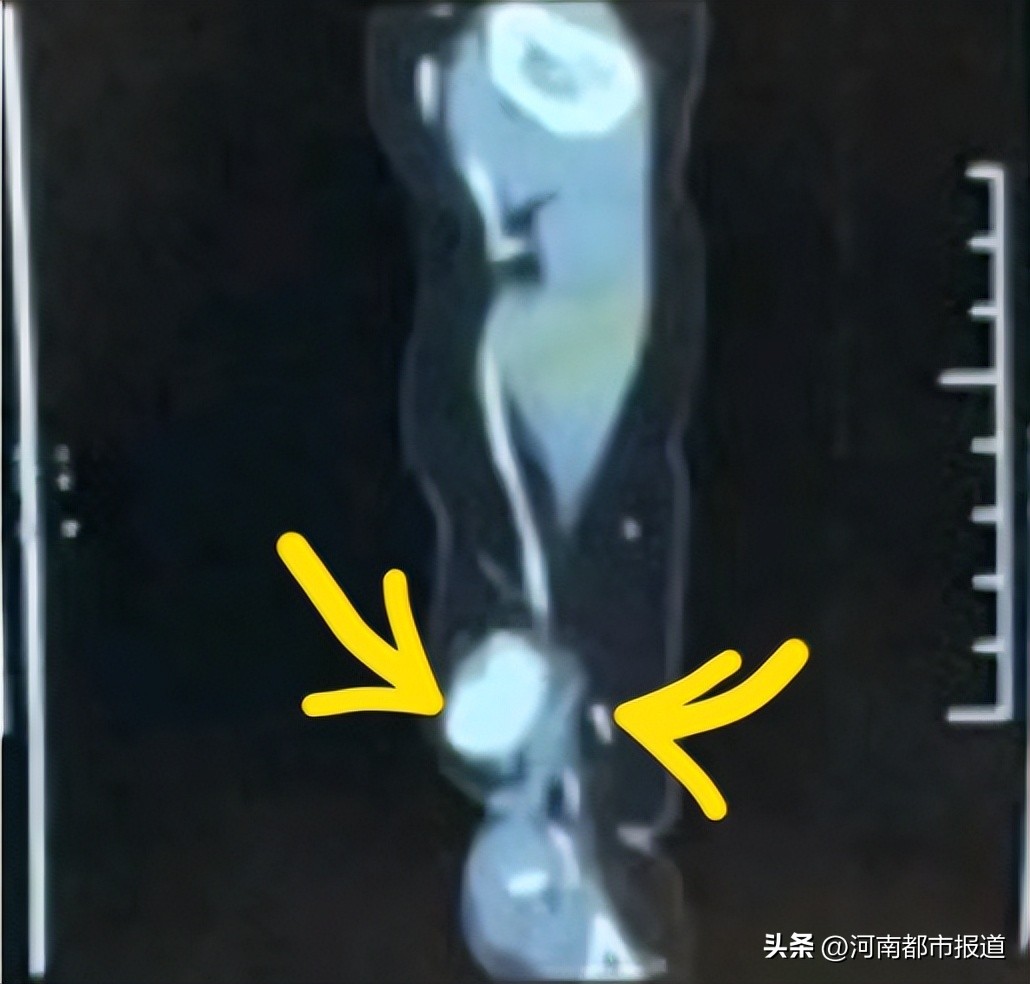

通过检查

发现祎祎情况十分危险

丁语决定立即为祎祎实施手术

微创介入+动脉瘤切除修复 的杂交手术

顶着巨大压力,所有人聚精会神,手术历时3个小时,通过血管造影“追凶”,外科手术“治本”,完美切除了动脉瘤,修复血管,而最终失血量仅有 5毫升。